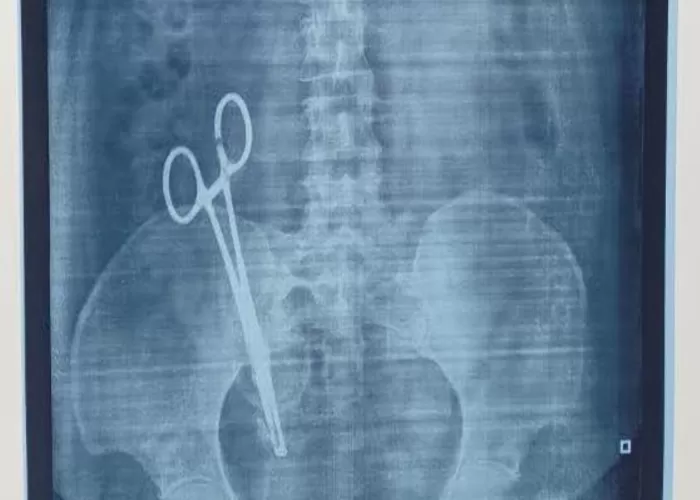

Saat dilakukan rontgen, hasilnya sungguh mengejutkan—terlihat jelas sepasang gunting bedah tertinggal di dalam perutnya.

Fakta ini menjadi pukulan keras bagi keluarga Sandhya, sekaligus menimbulkan kemarahan dan kekecewaan yang mendalam.

Tak lama setelah itu, Sandhya segera dirujuk ke King George's Medical University (KGMU) untuk menjalani operasi pengangkatan gunting tersebut.

Prosedur yang rumit berhasil dilakukan, dan gunting bedah itu akhirnya dikeluarkan dari dalam tubuhnya.